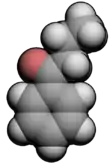

3D model (JSmol) |

Butyrophenone is an organic compound with the formula C6H5C(O)C3H7. It is a colorless liquid.

The butyrophenone structure—a ketone flanked by a phenyl ring and a butyl chain—forms the basis for many other chemicals containing various substituents. Some of these butyrophenones are used to treat various psychiatric disorders such as schizophrenia, as well as acting as antiemetics.[1]